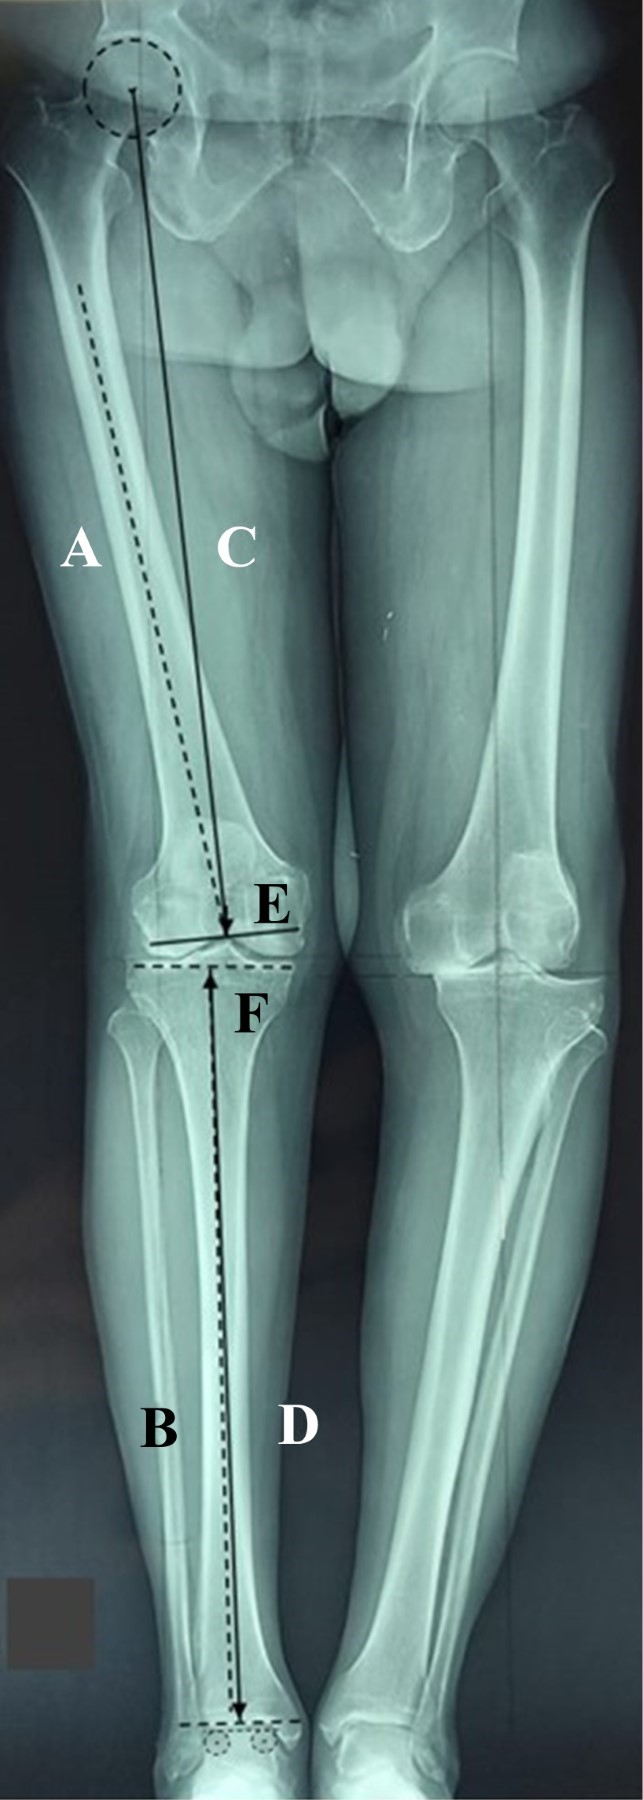

La necesidad de artroplastia total de rodilla está aumentando considerablemente y uno de los objetivos es lograr la alineación coronal postquirúrgica. La asistencia quirúrgica robótica consigue una alineación funcional, que es un ángulo cadera-rodilla-tobillo de 0°. Sin embargo, no es posible ofrecer cirugía asistida por robot a todos nuestros pacientes, por lo que debemos incluir la radiografía AP de soporte de peso de cadera a tobillo de cuerpo entero en la planificación preoperatoria para obtener una alineación de "zona segura", que es un ángulo postquirúrgico cadera-rodilla-tobillo de 0 ± 3°. ¿Cómo podemos conseguir una artroplastia total de rodilla con alineación de "zona segura" en pacientes con deformidad extraarticular?

Figura 1